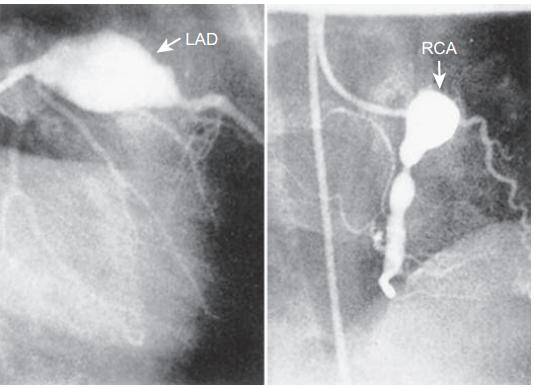

CAA位于心外膜冠状动脉,最常见于左前降支近端和右冠状动脉近端。按发生频率依次为:左冠状动脉主干、冠状动脉回旋支、右冠状动脉远端,以及冠状动脉后降支在右冠状动脉上的起始处。CAA好发于分支处,这提示了剪切应力的病理学作用。

CAA可以呈囊状、梭状或膨胀状(弥漫性扩张且无节段性动脉瘤)。其形状和大小随时间推移而演变。例如,最初表现为膨胀状的动脉瘤可在数周内演变为节段状或珠状。

6岁儿童的川崎病的冠状动脉造影图,巨大冠状动脉瘤,参考6